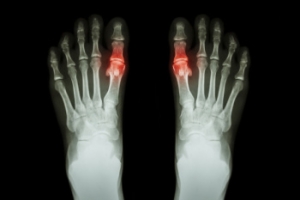

Gout in Teenagers

Gout is a crystalline inflammatory arthritis caused by the buildup of uric acid crystals within the joints. Although it is more common in adults, the prevalence of gout among teenagers is increasing due to obesity, poor diet, and certain medical conditions. It often affects the big toe, causing sudden joint pain, redness, swelling, and warmth. Repeated flare-ups may lead to joint deformities and, in severe cases, may contribute to kidney dysfunction and other systemic concerns. Risk factors include family history, metabolic disorders, and high consumption of sugary beverages or processed foods. A podiatrist can diagnose gout, manage painful symptoms, and coordinate comprehensive care. If your teenager has symptoms of gout, it is suggested that you consult a podiatrist who can provide an accurate diagnosis and relief options.

Gout is a form of arthritis that is characterized by sudden, severe attacks of pain, redness, and tenderness in the joints. The condition usually affects the joint at the base of the big toe. A gout attack can occur at any random time, such as the middle of the night while you are asleep.

Gout

Gout is a form of arthritis that is caused by a buildup of uric acid crystals in the joints. This considered to be one of the most frequently recorded medical illnesses throughout history. Gout occurrences in the US have risen within the past twenty years and the condition now affects 8.3 million people which is 4% of all Americans. Researchers have found that gout affects men more than women and African-American men more than white men.

Symptoms of gout are warmth, swelling, discoloration, and tenderness in the affected joint area. The small joint on the big toe is the most common place for a gout attack to occur.

Diagnosis for gout is done by checking the level of uric acid in the joints and blood. Your podiatrist may also prescribe medicine to reduce uric acid buildup in the blood, which will help prevent any gout attacks.